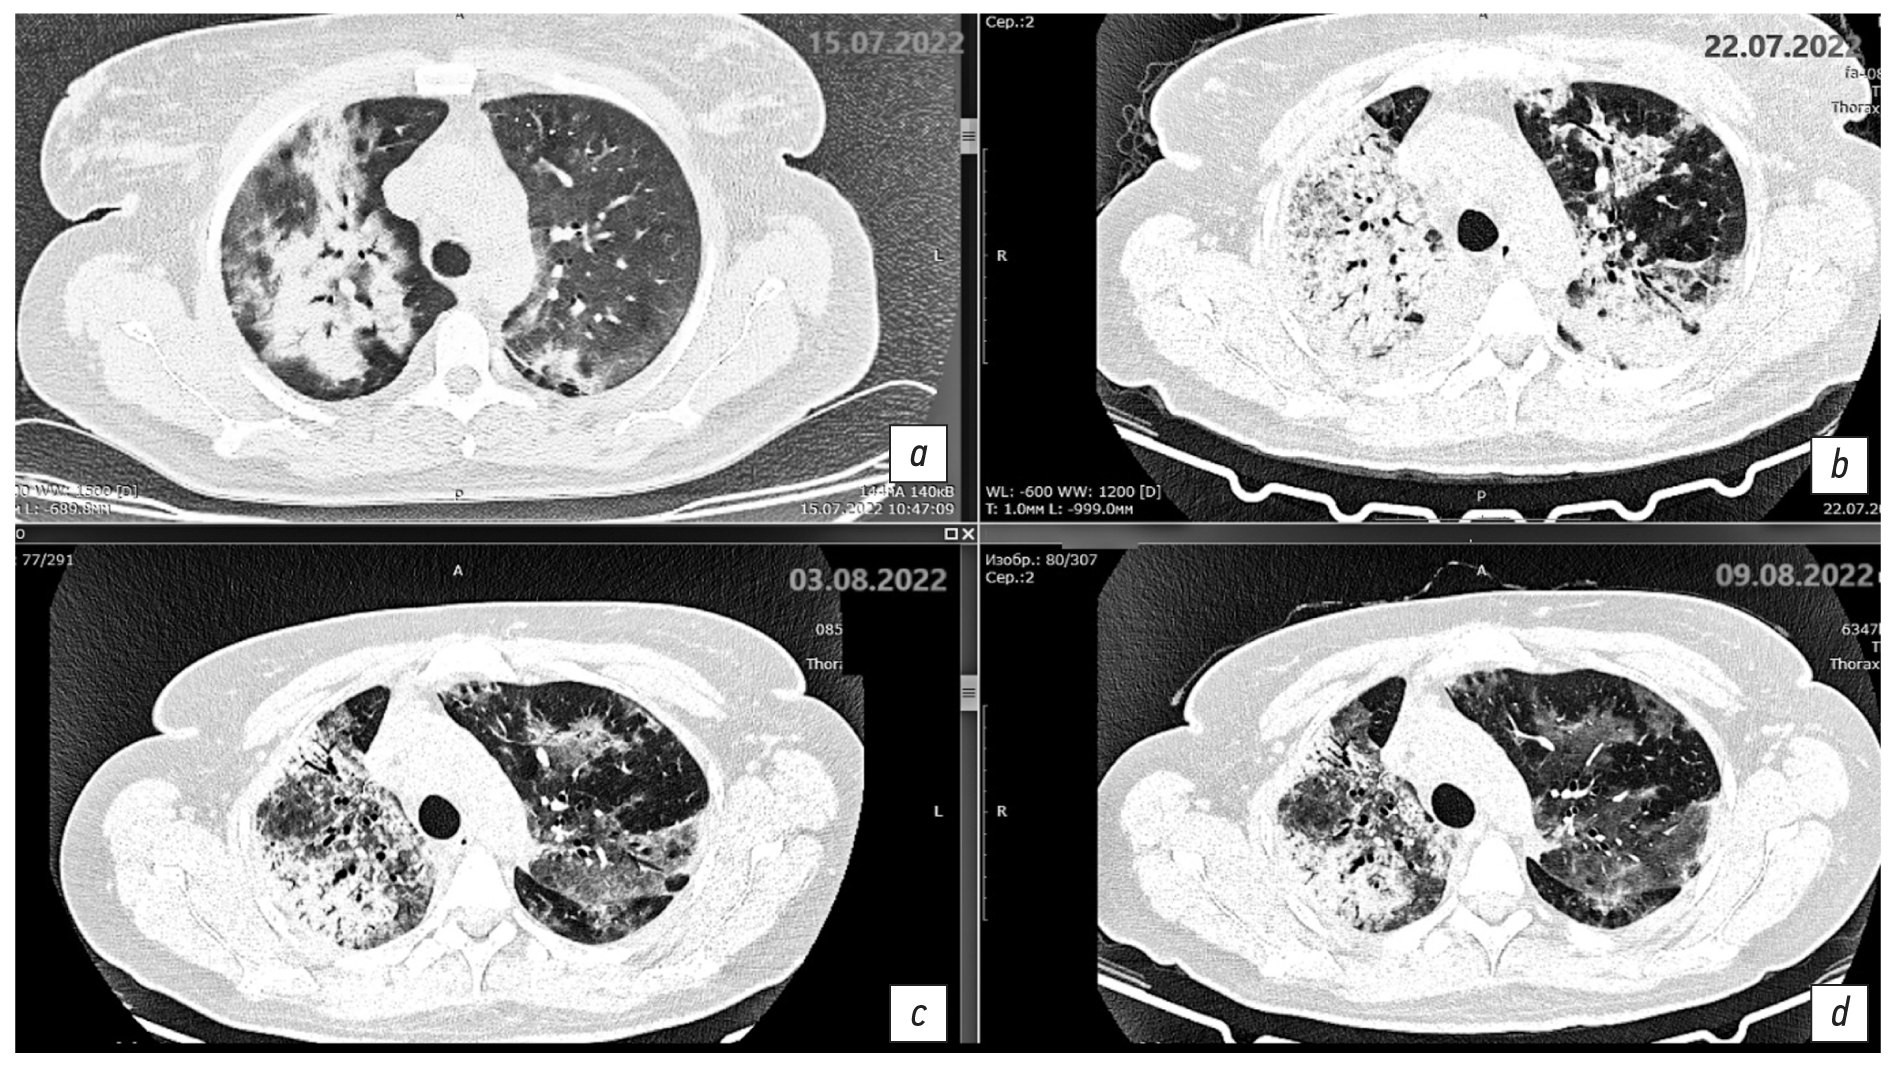

Fig. 1. Axial sections at the level of the aortic arch, pulmonary window. Changes in the areas of heterogeneous infiltration: a: chest CT scan dated July 15, 2022, day 11 of the disease, day 1 of hospitalization; b: chest CT scan dated July 22, 2022, day 18 of the disease, day 7 of hospitalization; c: chest CT scan dated August 3, 2022, day 30 of the disease, day 19 of hospitalization; d: chest CT scan dated August 9, 2022, day 36 of the disease, day 25 of hospitalization.

Fig. 2. Axial sections at the level of the main bronchi, pulmonary window. Changes in the areas of heterogeneous infiltration: a: chest CT scan dated July 15, 2022, day 11 of the disease, day 1 of hospitalization; b: chest CT scan dated July 22, 2022, day 18 of the disease, day 7 of hospitalization; c: chest CT scan dated August 3, 2022, day 30 of the disease, day 19 of hospitalization; d: chest CT scan dated August 9, 2022, day 36 of the disease, day 25 of hospitalization.

Fig. 3. Axial sections at the level of the basal parts of the lungs, pulmonary window. Changes in the areas of heterogeneous infiltration. a: chest CT scan dated July 15, 2022, day 11 of the disease, day 1 of hospitalization; b: chest CT scan dated July 22, 2022, day 18 of the disease, day 7 of hospitalization; c: chest CT scan dated August 3, 2022, day 30 of the disease, day 19 of hospitalization; d: chest CT scan dated August 9, 2022, day 36 of the disease, day 25 of hospitalization.

On day 18 of the disease and day 7 of the hospital stay, the chest CT scan dated July 22, 2022 (Fig. 1b, 2b, 3b) revealed negative changes in bilateral multifocal pneumonia and weakly negative changes in bilateral pneumothorax and hydropericardium. Moderate intrathoracic lymphadenopathy without changes and a focal mass in the left breast were observed. Antibiotic therapy was re-adjusted; rifampicin was discontinued, and intravenous tigecycline 100 mg daily was added to levofloxacin 1 g daily. This regimen demonstrated gradual positive changes.

Since August 1, 2022 (day 28 of the disease, day 17 of inpatient treatment), the patient’s condition was of average severity, with normalized body temperature, decreased symptoms of respiratory insufficiency, and persistent weakness. The air saturation was 89% and 97% with humidified insufflation at 4 L/min. The chest CT scan dated August 3, 2022 revealed mixed changes of bilateral multifocal pneumonia. The left lung exhibited positive findings, whereas the right lung displayed cavitary lesions. The presence of a dilated bronchial lumen and heterogeneous infiltration were suspected. The regression of bilateral hydrothorax was accompanied by negative changes in hydropericardium.

Description of the chest CT scan dated August 3, 2022 (Fig. 1c, 2c, 3c): The lung volume increased due to regression of fluid in the pleural cavities on both sides. Previously, the maximum fluid level was 21 mm on the right side and up to 19 mm on the left side, with a flow along the interlobular pleura up to 17 mm. Multiple segments of the lungs exhibit extensive confluent areas of heterogeneous infiltration, predominantly of the consolidation type. Within these areas, the lumen of dilated bronchi and a ground glass appearance is observed, accompanied by a single discoid atelectasis. The changes have no preferred localization. A marked continuous reduction in the extent and intensity of changes in the left lung is observed, with preserved ground-glass changes and consolidation (S1/2).

The extent of changes in the right lung remains unaltered. However, an increase in consolidation is observed in the upper regions. Additionally, heterogeneous infiltration in the right lung in S6 and S10 segments caused cavitary lesions up to 9 × 7 mm and 4 × 5 mm, respectively. This phenomenon is likely attributable to the dilation of the bronchial lumen, heterogeneous expansion of infiltration, or the formation of a destruction cavity.

The paratracheal lymph nodes are 12 mm in diameter, whereas the bifurcation lymph nodes measure up to 14 × 18 mm (previously 17 × 22 mm). The heart is unremarkable. Fluid in the pericardial cavity supradiaphragmatically is up to 14 mm (previously 10 mm). A focal mass is present in the upper-inner quadrant of the left breast, measuring up to 11 mm, with a density of 22 HU, and insufficiently clear contours. Results: Bilateral multifocal pneumonia with mixed changes (positive in the left lung). Cavitary lesions in the right lung may be characterized by dilated bronchial lumen, heterogeneous infiltration, or a destruction cavity. Follow-up chest CT is recommended. There is evidence of bilateral hydrothorax regression. The hydropericardium shows negative changes. Moderate intrathoracic lymphadenopathy exhibits weakly positive changes. A focal mass in the left breast is observed.

The antibiotic therapy was continued at the same dosage, prophylaxis of thromboembolic events was administered, and periodic oxygen therapy was provided.

On August 10, 2022 (day 37 of the disease, day 26 of hospitalization), the patient’s condition was deemed satisfactory. The patient reported a rare dry cough and slight exertional dyspnea. The patient’s air saturation was 97%. The chest CT scan dated August 9, 2022 (Fig. 1d, 2d, 3d) demonstrated positive changes in bilateral multifocal pneumonia, with a decrease in intensity. Additionally, there were no changes in cavitary lesions in the right lung, which could be attributed to dilated bronchial lumen or heterogeneous infiltration. Hydropericardium also showed positive changes.

Description of the chest CT scan dated July 15, 2022 (Fig. 1a, 2a, 3a): The lungs are fully expanded. Pneumatization is diffusely reduced. The pulmonary pattern is deformed. Both lungs show multifocal infiltrative changes of the pulmonary parenchyma of a ground-glass type with reticular shadows and peribronchial consolidation type. The infiltrative changes are located randomly. The parenchyma is visibly involved. Up to 30% and 60% of the pulmonary parenchyma is affected in the left upper and lower lobes, respectively. Up to 60% of the pulmonary parenchyma is affected in the right upper and lower lobes. The volume of the affected parenchyma in the left lung is up to 45% and less than 70% in the right lung. The total percentage of lung damage reaches 70%. The degree of severity is at the CT3 level.

The configuration and lumen of the trunk bronchi are unremarkable. The mediastinum is of normal shape and location. A layer of free fluid, up to 20 mm in thickness, is observed in the upper aortic pouch. The intrathoracic lymph nodes are indurated and enlarged. The para-aortic group is 11 mm along the short axis, the paratracheal group is up to 12 mm, the bifurcation group is up to 17 mm, and both bronchopulmonary groups are up to 12 mm. The major vessels are of normal structural organization and sizes. In both pleural cavities, a layer of free fluid is observed, measuring up to 15 mm along the posterior wall on the right side and up to 5 mm on the left side. Results: Bilateral multifocal pneumonia, intermediate probability of COVID-19 pneumonia (pneumonia of other etiology?), CT3, 65%–70%. Enlarged mediastinal lymph nodes, hydropericardium, bilateral hydrothorax, and focal mass in the left breast.